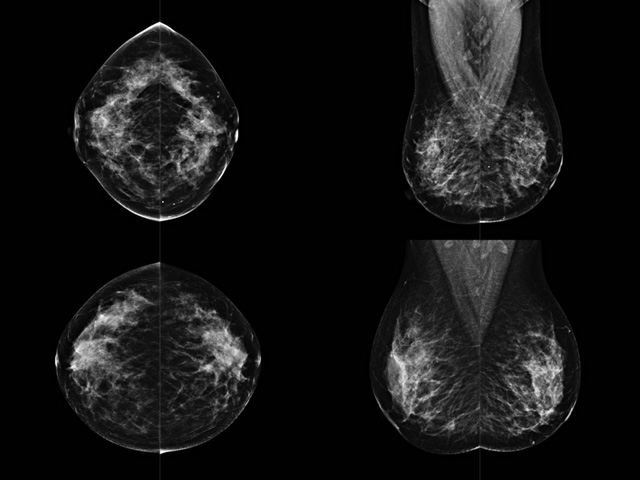

乳房檢查時候要注意一些細節(jié),需要更深入的了解這樣才能使檢查更準確。乳腺DR是乳腺癌的篩查診斷工具設(shè)備。是乳房方面檢查的重要影像方法。它可以臨床檢查出早期的乳腺癌??梢耘袛嗔夹詯盒?。因為它可以檢查出早期的病變。對良性惡性檢查的準確率達到90%以上。發(fā)病高峰年齡為45歲到54歲。50歲檢查出來乳腺癌病患,可以讓死亡率下降3成。所以30-40歲女性每年做一次乳腺DR檢查。40歲以上就一年兩次。如果家族史有乳腺癌的30歲以下也需要做檢查。清晰顯示乳腺各層組織嚴重的乳腺增生,乳腺炎,乳腺外傷也建議1年檢查一次。極大提高了早期乳腺癌的敏感度和診斷率。

大角度、高質(zhì)量的乳腺檢查,可以讓女性帶來身體健康安全。為醫(yī)生提供了高清影像數(shù)據(jù)。乳腺檢查時候各個部位影像顯示出來。白色乳腺導(dǎo)管跟纖維結(jié)締組織。模糊的是脂肪。病變一般是不透明的白色。有需要放大來檢查。乳腺DR沒有重疊偽影。輻射劑量更少。因為乳腺癌發(fā)病每年都有所提高,對女性都造成了嚴重的身體健康危害。早做檢查早治療是不可忽視的舉措。可以大大的降低死亡率。保證身體健康。一般檢查避開經(jīng)期,來完7天左右是最佳的檢查時間。絕經(jīng)的女性就沒有要求。孕婦不參加乳腺DR檢查, 6個月內(nèi)準備妊娠的婦女也不宜行此檢查。